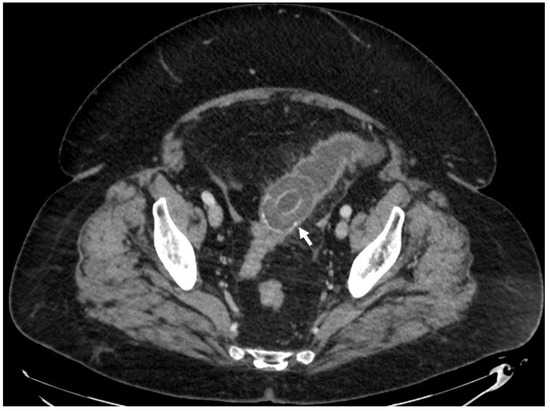

| F, 69 | 12 | III | Colonoscopy | 115 | Sigmoid colon | 5 × 4 cm | - | 10 | Good: recovery |